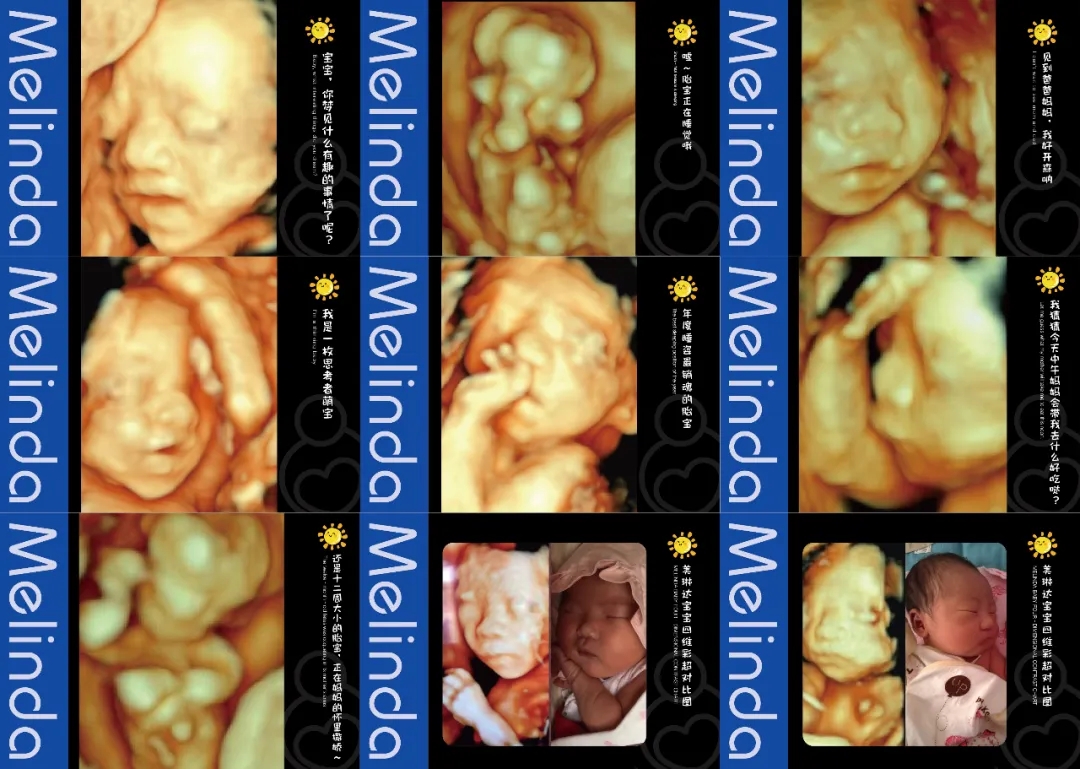

(美琳达四维宝宝照片)

注重孕妈体验度-检查更舒适入院时,导医客服引领陪同检查,检查结果出来后专人电话通知。候诊时,大厅放置舒适的沙发可供休息,客服也会为客户提供饮品和食品等。检查时,四维彩超诊室设置适宜观看的高清电视屏幕,双屏互动模式,检查时孕妈可以清晰看见医生操作。检查床旁放置舒适纯皮沙发,支持家属陪伴检查。重要的是,美琳达也会提供胎儿写真照片,留作纪念。

(明星主播东玥两次四维检查胎宝照片对比)一次检查就可以享受到全部服务你就说香不香?还没有预约的孕妈,抓紧时间吧!